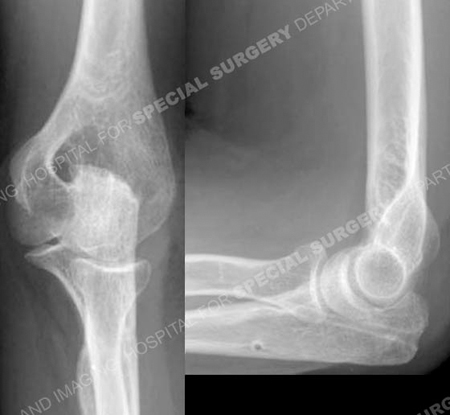

Anteroposterior and lateral radiographs 10 months following fracture surgery illustrating a

healed olecranon fracture in excellent alignment.